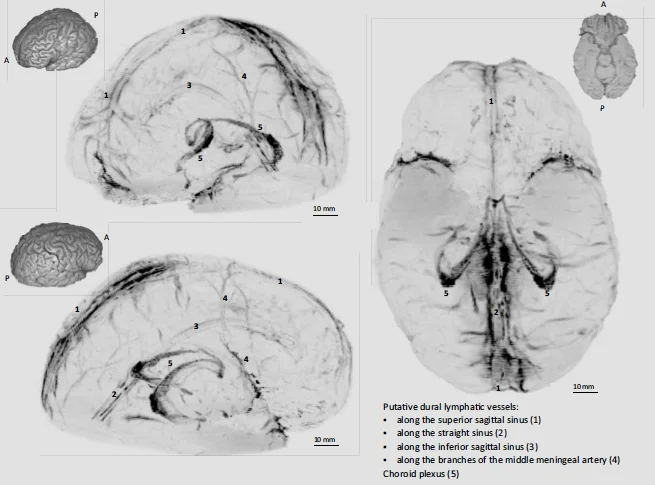

3D rendering of human dural lymphatics (curtesy of elifesciences.org)

The lymphatic system of the body circulates and filters the fluid that bathes body cells to remove toxins and fight infection. Brain cells, just like body cells, produce waste products as a result of their metabolic functioning but no brain lymphatic system had been found until most recently. In October 2017 researchers at the U.S. National Institute Neurological Disorder and Stroke published their discovery of a system of lymphatic vessels that are embedded in the dura mata, the leathery membrane that covers the brain. The senior researcher of the group, Daniel Reich, is an expert in inflammatory brain disease, specifically multiple sclerosis (MS). An important element in MS as well as other neurodegenerative disease may be a failure in the brain lymphatic system. So maintaining healthy functioning of the brain lymphatic system may help prevent and treat these diseases.